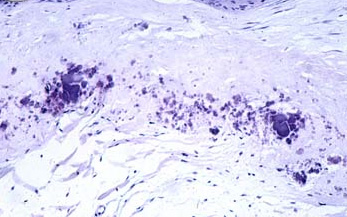

翼状胬肉显微解剖图

翼状胬肉

(来源:正大光明)(责编:xhhdm)